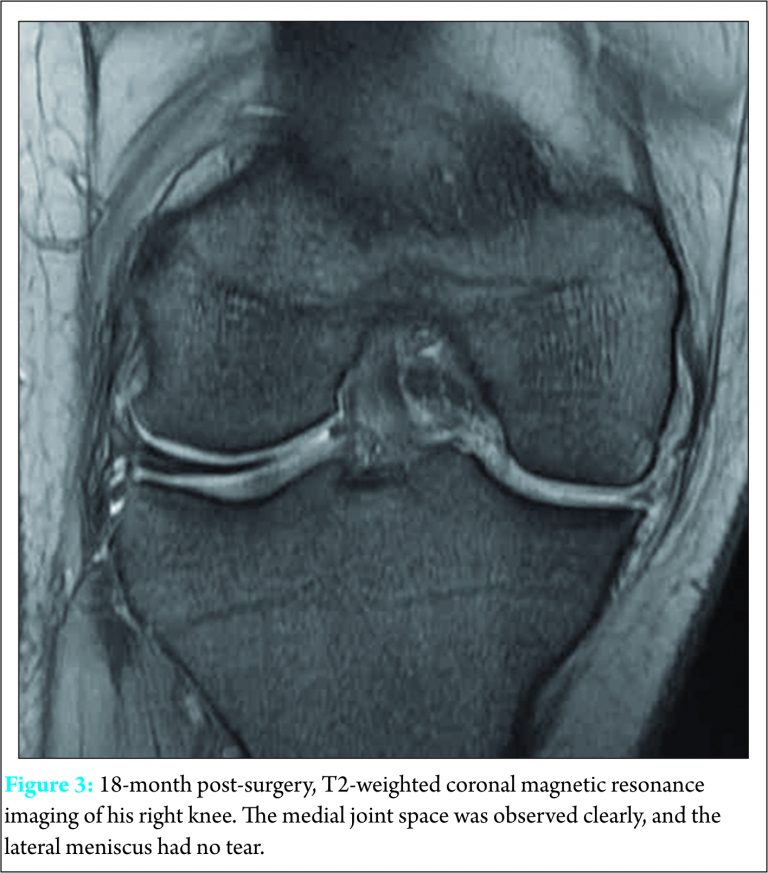

We performed arthroscopic partial meniscectomy of the medial discoid meniscus. We performed no surgical procedure for the lateral discoid meniscus because the patient had no clinical symptoms and the lateral discoid meniscus had no tear. We also checked the stability of the connection between the meniscus and the posterior soft tissue both medially and laterally (Fig. 2). Walking was allowed the day following the operation. Three months later, the patient had no pain or symptoms in his right knee and resumed playing sports. At the last follow-up, 18 months post-surgery, he had no limitation of motion, could play sports with full effort, and was satisfied with the result. The medial joint space in his right knee was observed clearly on MRI, and the lateral meniscus had no tear (Fig. 3).